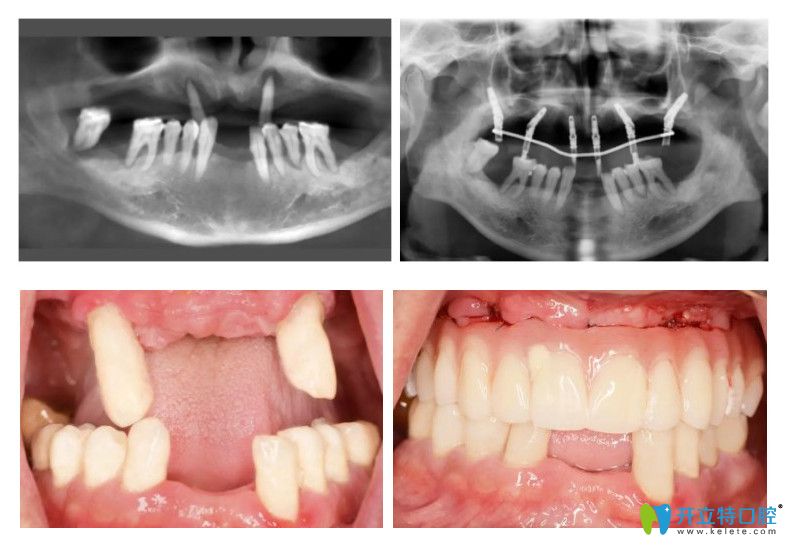

種植半口牙的病例

60歲的張大爺,得了牙周病,牙齒脫落了很多,由于病例較復(fù)雜,跑了好些口腔醫(yī)院都沒法種植,通過朋友介紹來到圣貝口腔就解決了半口牙齒種植,用了6顆種植體,就恢復(fù)了半口牙齒的咀嚼功能!